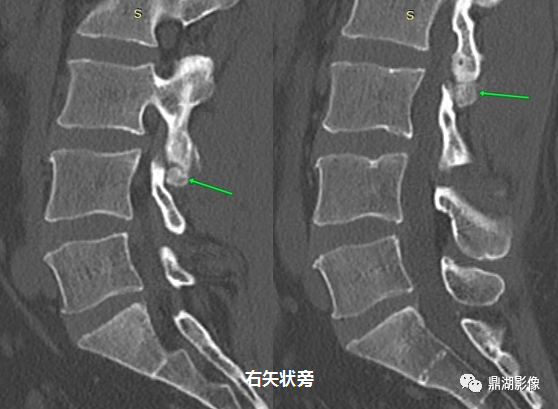

男性患者,40岁,腰背部疼痛,否认外伤史。

奥本海默小骨(Oppenheimer ossicle)

奥本海默小骨于 1942 年由Albert Oppenheimer首次描述,是关节突次级骨化中心不融合的结果。

好发于腰2和腰3椎体,主要表现为腰椎下关节突的游离小骨,也可发生于上关节突。通常无症状,多在影像学检查中偶然发现。

影像学特征:奥本海默小骨具有光整的骨皮质,相邻小关节的滑膜囊可与奥本海默小骨与关节突之间的裂隙相通。

在影像学上,需与关节突骨折相鉴别:奥本海默小骨形态规则、骨皮质光整、连续。